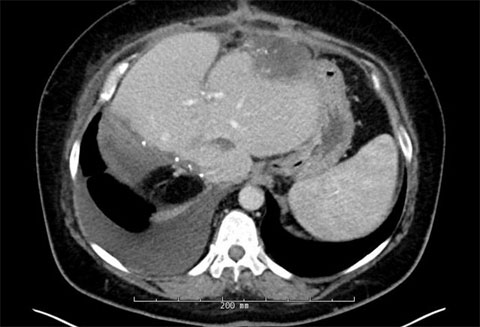

Post-first-surgery MRIs

We identified 12 total lesions on the patient’s liver; five of these were in segment 2, one was in segment 1, four were in segment 3 and two were in segment 4A.

In the following order, we used microwave ablation the following lesions: lesions 10 on the middle hepatic vein, lesion 9 in segment 4B, lesion 3 in segment 2, lesions 2 and 5 in segment 3, then lesion 4.

We then proceeded with resection of the following lesions in this order: partial hepatectomy of lesion complex 8, partial hepatectomy of lesions 6 and 7, and a wedge resection lesion 11. When we encountered the caudate lesion, it was superficial and would be too difficult to retract; instead, we performed an ablation on it instead.

All of the lesions showed signs of extensive regression from chemotherapy.